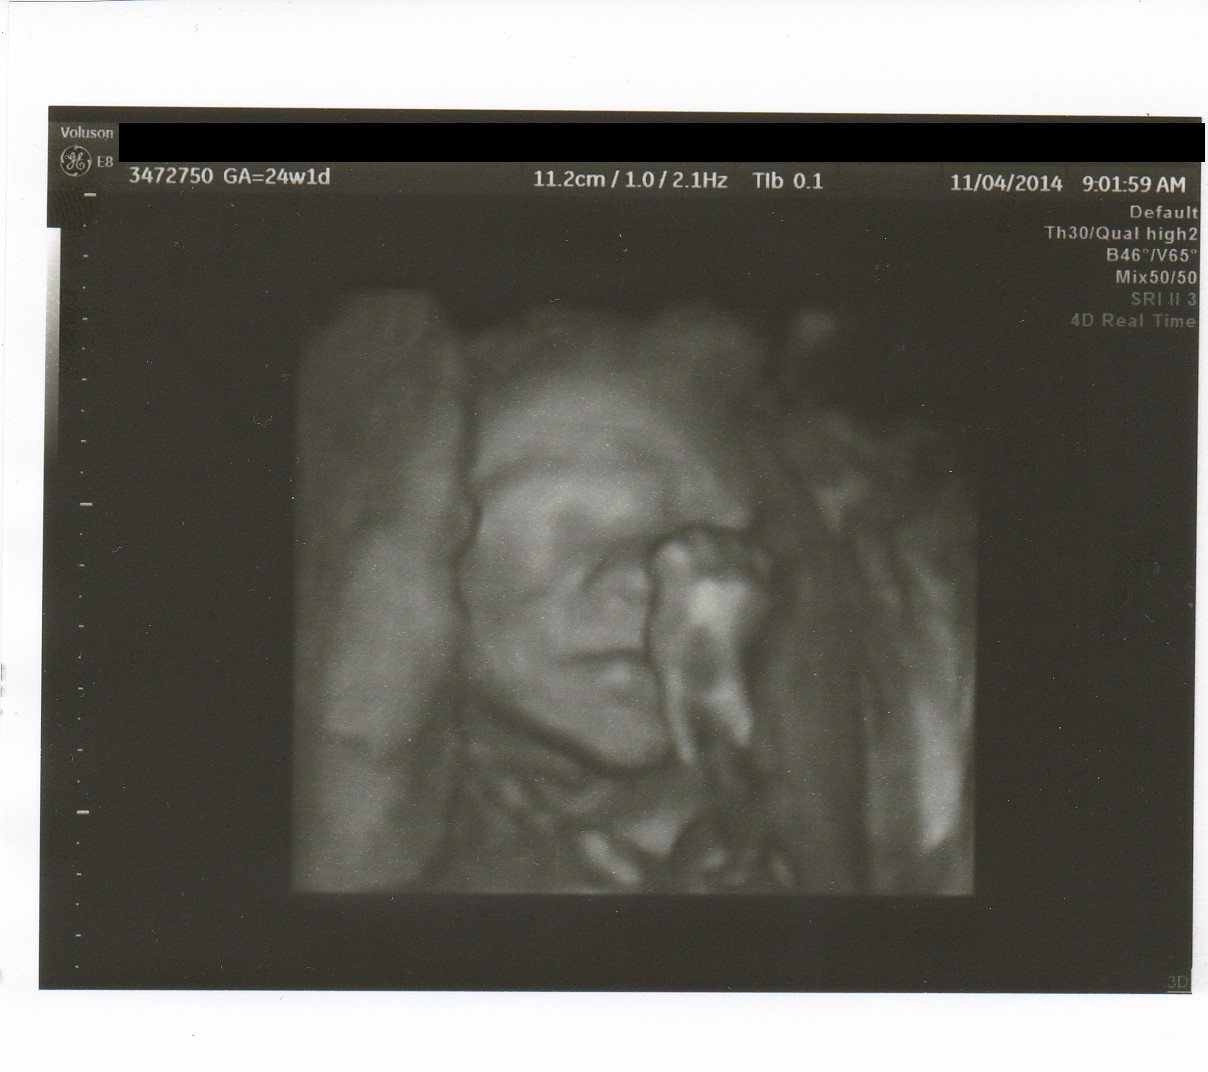

I've been getting precautionary cervical length measurements every 2 weeks since around 12 weeks and as of today I'm done with them! MFM gave me a great report and my cervix hasn't given him any reason to be concerned so he released me until December 2nd! He wants me to come in around then to get little man's measurements and make sure I'm not funneling or anything but otherwise I shouldn't have to see him between now and then! By this time with DS, I was already in preterm labor and on bed rest so I'm hopeful that this LO keeps up his good behavior and this pregnancy stays uneventful! I've been extremely fortunate to have such a great team between my OB and MFM (and their techs, of course!!) and I'll definitely miss getting to see my bubba every 2 weeks, but it's so nice to have him tell me it was safe to exhale and that he doesn't want to see me any time soon :)image